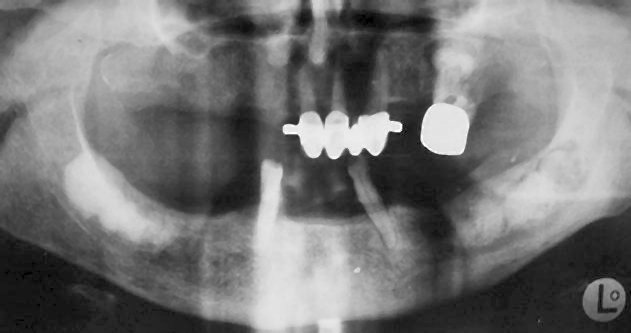

Διάχυτη οστεϊνική-οστική δυσπλασία (ακτινοσκιερός τύπος) .

Ακτινογραφική Εικόνα

- Αρχικό στάδιο: Διαύγαση με μάλλον σαφή όρια.

- Ενδιάμεσο στάδιο: Εναπόθεση σκιάσεων στο κέντρο της βλάβης (συνδυασμός διαύγασης και σκίασης).

- Τελικό στάδιο: Σκίαση με σαφή όρια που περιβάλλεται από διαυγαστική άλω.